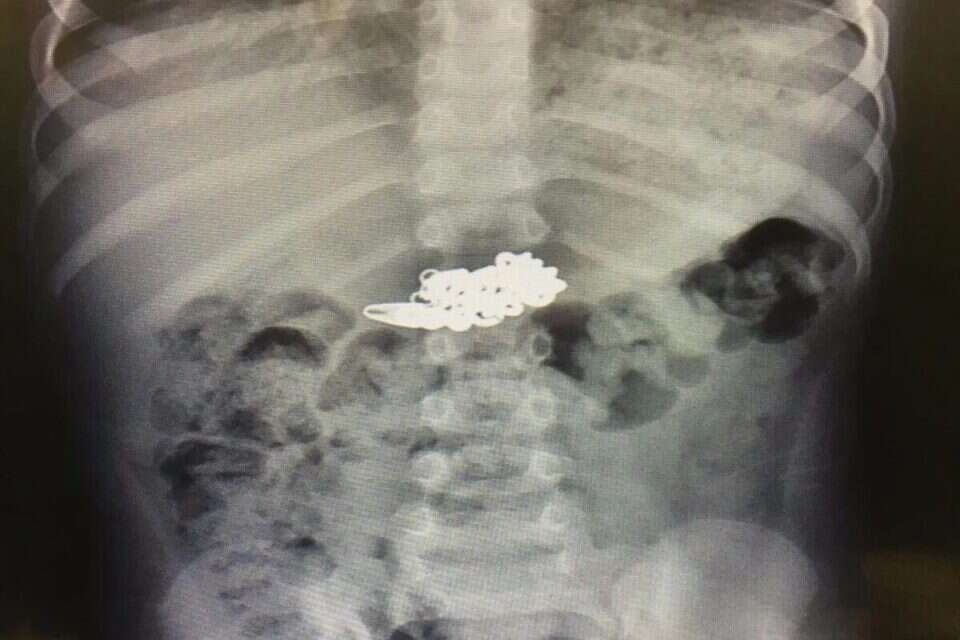

משום שהפעוט לא הראה כל סימפטומים ולא התלונן על כאבים, וכדי להימנע מבדיקה פולשנית בילד כה קטן, אושפז הפעוט להשגחה בזמן שהצוות עוקב אחר מצבו וממתין שהשרשרת תצא מגופו באופן טבעי. לאחר יומיים, משלא יצאה השרשרת, נבדק הפעוט שוב על מנת לאבחן את מיקומו של העצם הזר. מבדיקת צילום חוזר עלה כי השרשרת, שאורכה 10 ס"מ, התמקמה בקיבתו של הילד והוחלט שלא להמתין יותר ולשלוף אותה.

השרשרת לאחר שנשלפה מקיבתו של הילד // צילום: באדיבות ביה"ח רמב"ם